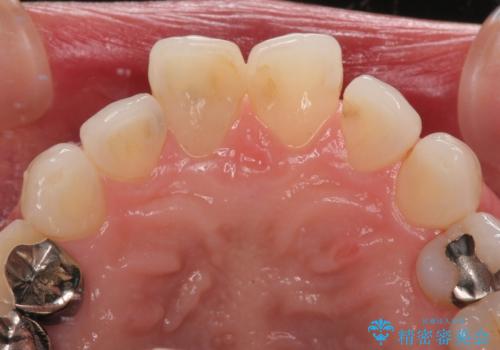

- 前歯の変色と、以前装着したクラウンが黄ばんできたことを気にして来院された患者様です。

前歯に変色が起こる場合、神経組織の失活により引き起こる可能性が高いため、診察を行ったところ、根尖部の病変や叩いたときの痛みなどが認められました。

まずは根管治療を行い、痛みの消退を確認してからオールセラミッククラウンによる補綴治療を行うこととしました。

前歯に痛みがあるという実感はなかったそうですが、診察で叩いたときの痛みを感じた際、今までに同様の痛みや違和感を感じたことがあったとのことでした。

初回の根管治療で痛みや違和感は消退したため、その後は速やかに補綴治療を行いました。